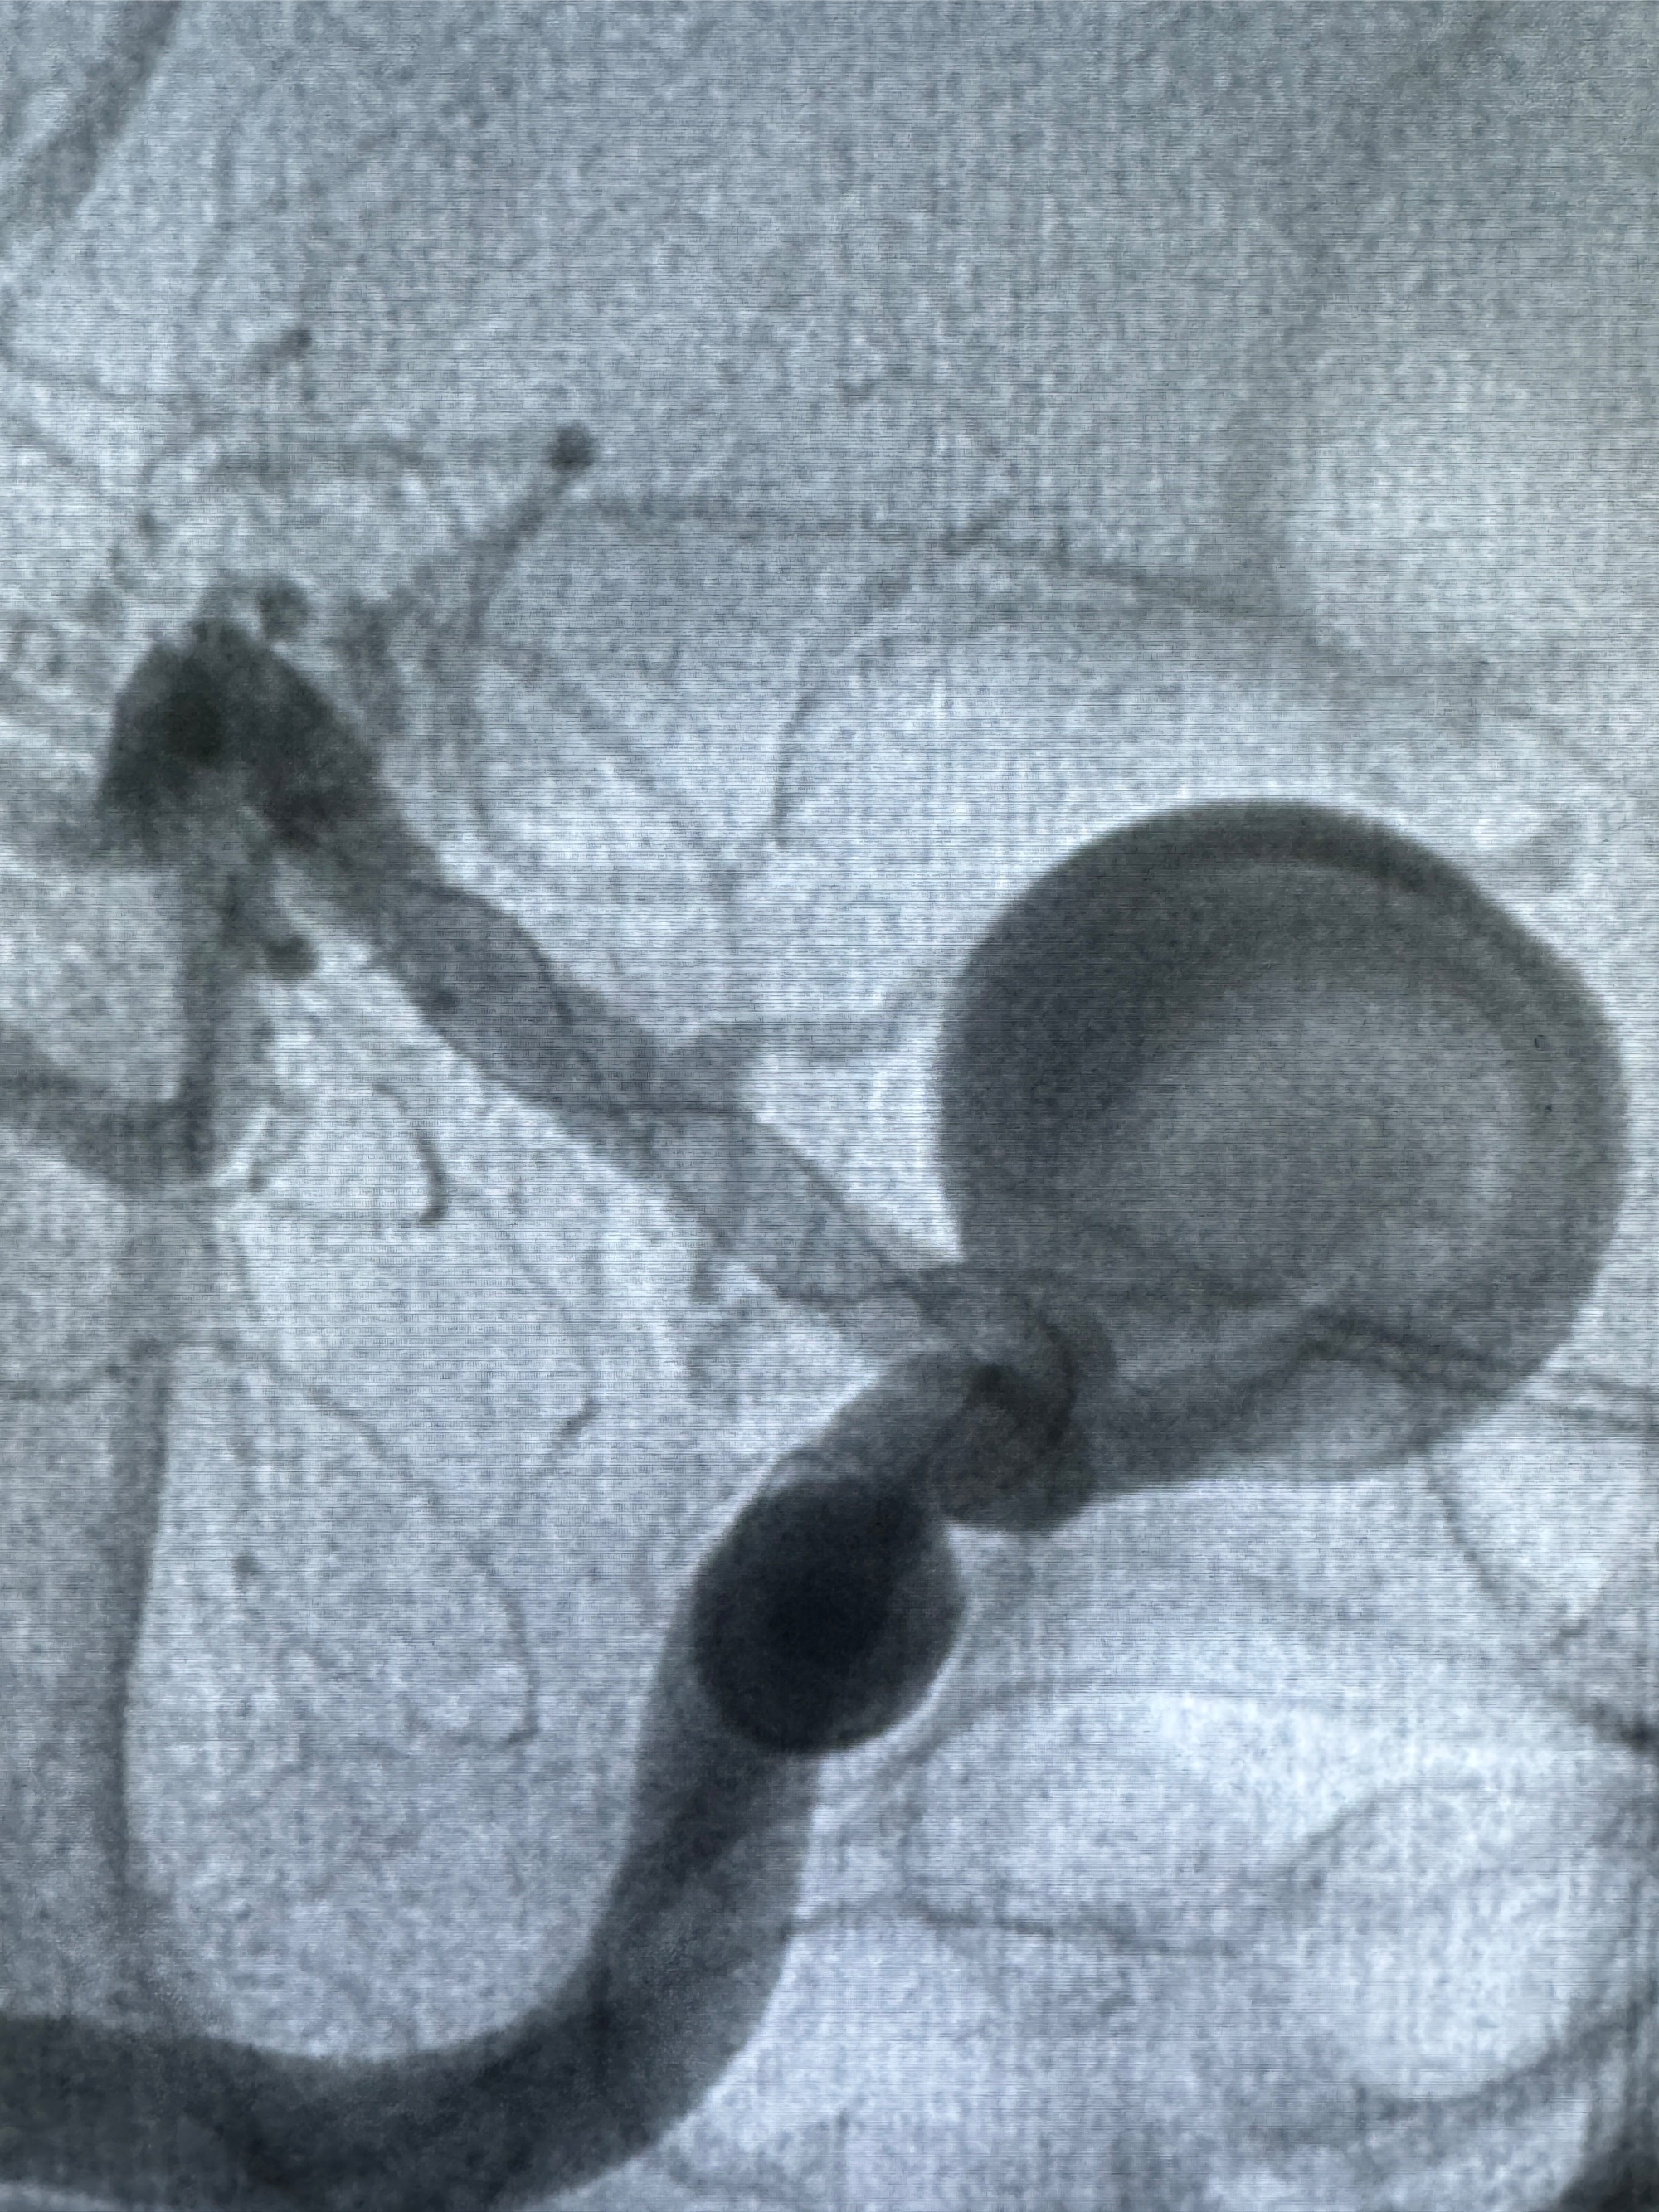

2023-12-08外院DSA:右侧颈眼动脉瘤,约13*12mm大小,压颈试验显示左右向及后向前代偿可

观察动脉瘤腔内的血流动力学情况